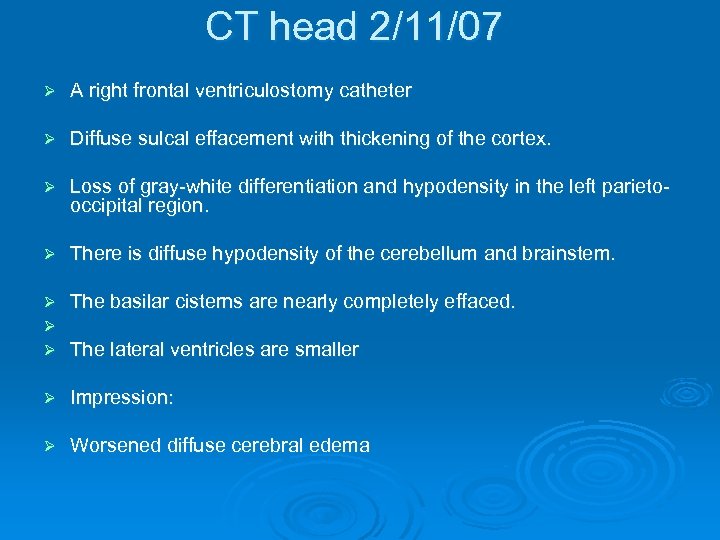

CT head 2/11/07 Ø A right frontal ventriculostomy catheter Ø Diffuse sulcal effacement with thickening of the cortex. Ø Loss of gray-white differentiation and hypodensity in the left parietooccipital region. Ø There is diffuse hypodensity of the cerebellum and brainstem. Ø Ø Ø The basilar cisterns are nearly completely effaced. Ø Impression: Ø Worsened diffuse cerebral edema The lateral ventricles are smaller